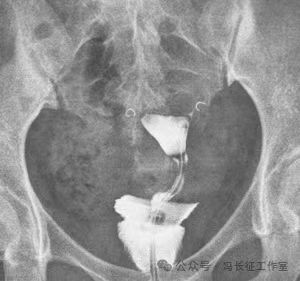

2013年在胃肠机上点片的造影片可以明确显示双侧输卵管间质部和峡部细,长度约4厘米。

2014年5月在DSA上行输卵管近段介入栓塞术

栓塞前造影也显示双侧输卵管间质部和峡部细长,适合栓塞。于是向双侧输卵管间质部和峡部各栓塞一枚3/2(长2厘米,一端直径小2毫米另一端直径大是3毫米,就是向宝塔一样,有时被称为塔圈)弹簧圈。